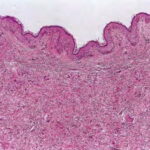

Histopathology. Histologic examination of the involved skin reveals considerable accumulations of swollen and irregularly clumped fibers staining like elastic fibers in the middle and lower thirds of the dermis; that is, they stain deeply black with orcein or Verhoetrs stain . Although normally elastic fibers do not stain with routine stains such as hematoxylin-eosin, the altered elastic fibers in pseudoxanthoma elasticum stain faintly basophilic because of their calcium imbibition. Staining for calcium with the von Kossa method also shows these fibers well. |